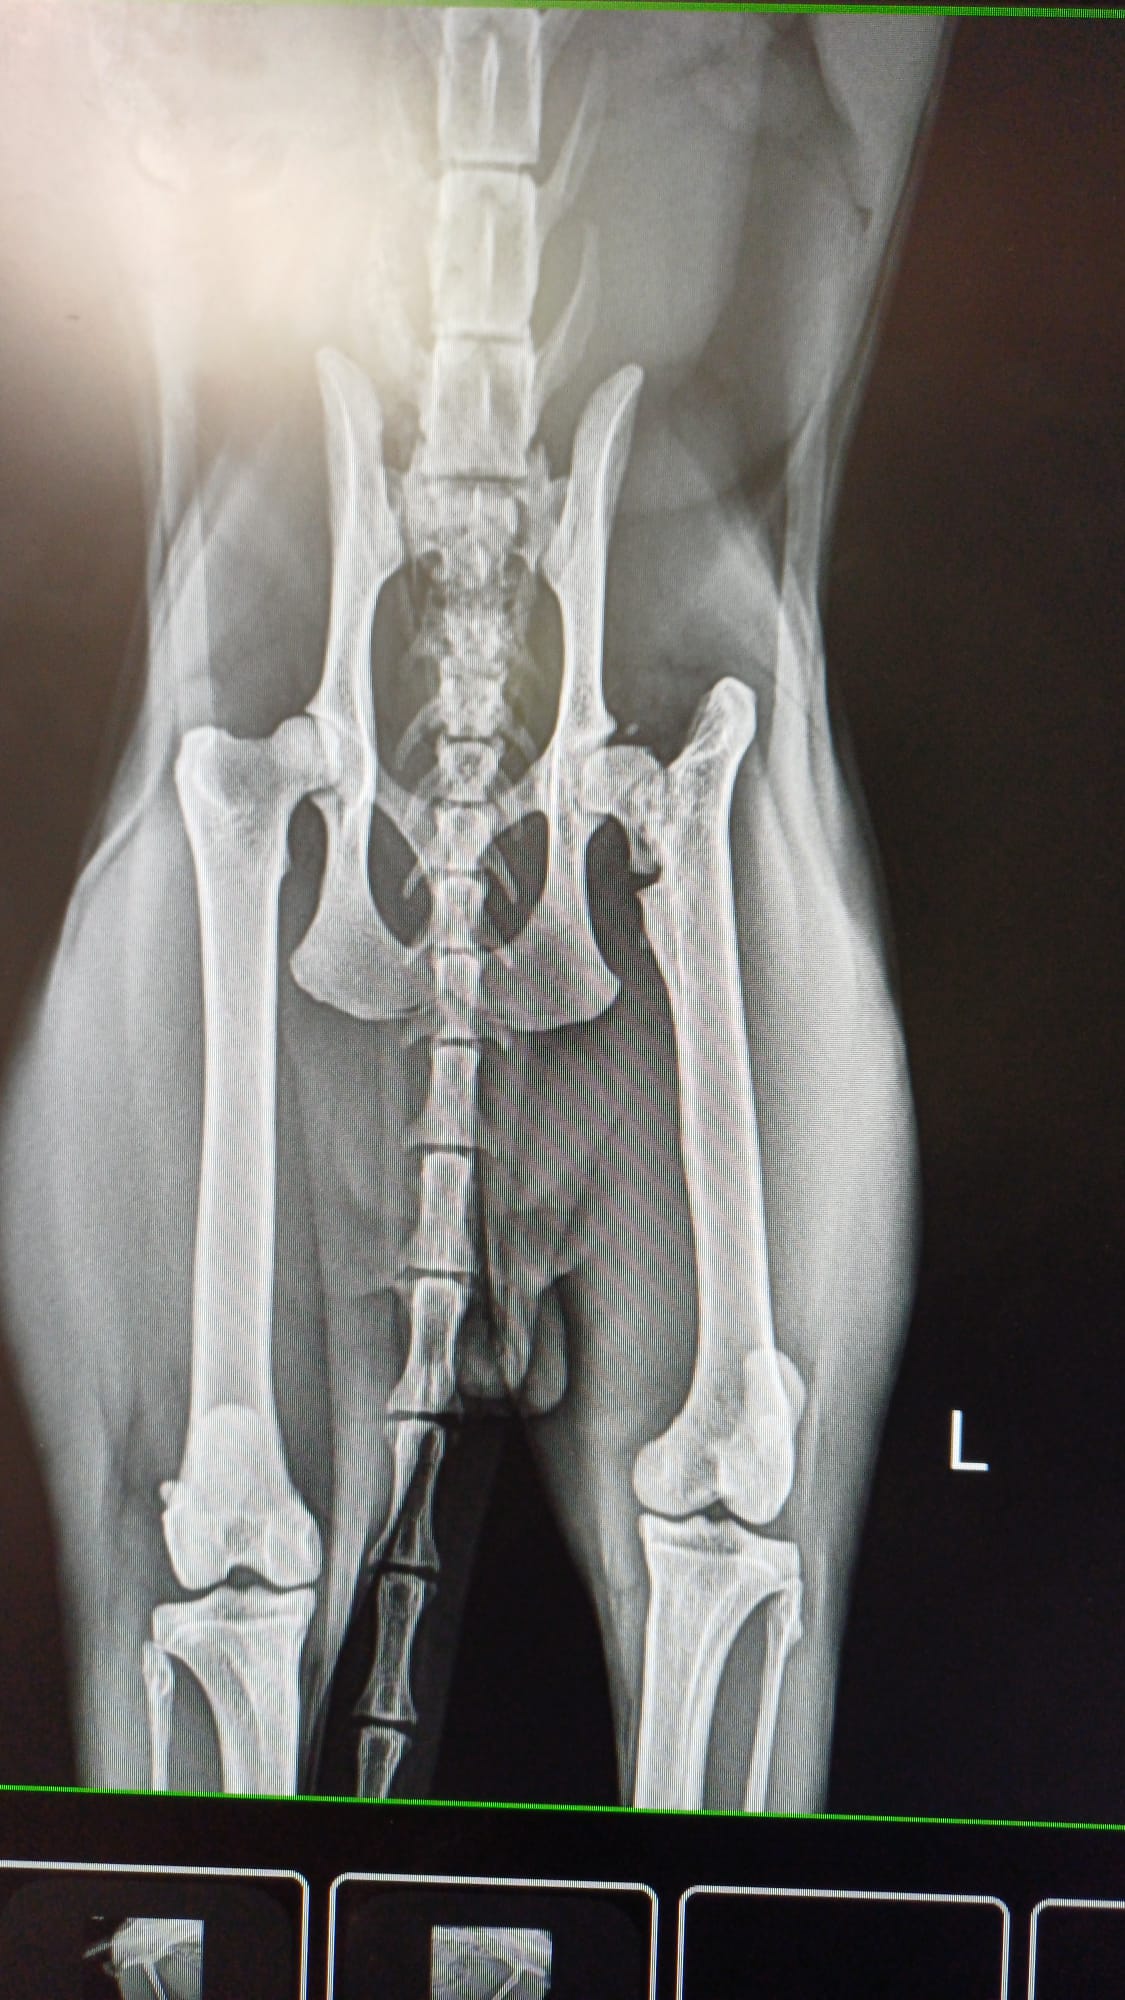

En septiembre cuando subimos a realizar las fotos del calendario vimos que no tenia masa muscular en una de las patas traseras, además de una cojera bastante importante. Nos lo llevamos a nuestros veterinarios donde se vio que tenia una Fractura antigua de la cabeza del femur. Al día siguiente se le realizo una artroplastia de la cabeza del femur. Ahora guarda reposo relativo en nuestro refugio. Es un gato adorable que nos ha robado el corazón desde el minuto 0.